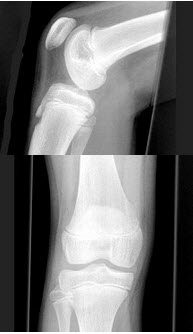

110、单项选择题

女,根据其正常膝关节影像图像,判断其最可能的年龄()

A.5岁左右

B.11岁左右

C.17岁左右

D.23岁左右

E.29岁左右